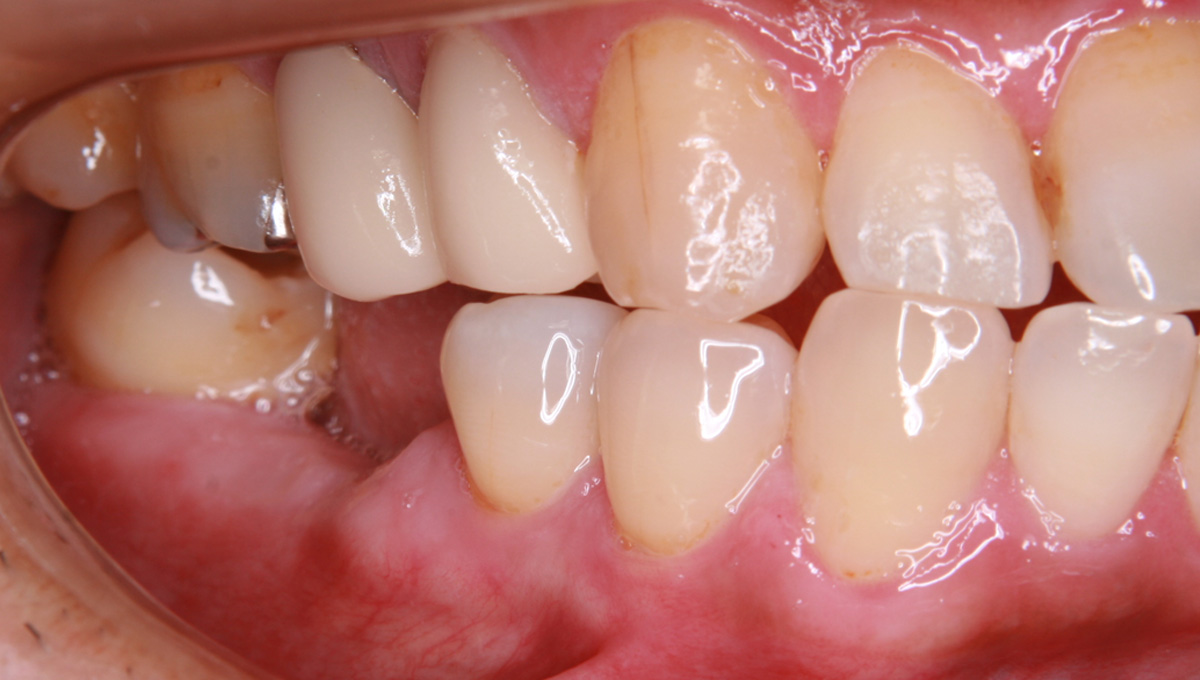

抜歯した箇所にインプラント治療を行った例

術前・術後の比較

インプラント手術から3ヵ月後、型どりをして、仮歯を製作しました。

レントゲン画像 -

仮歯の調整期間を経て、セラミックの歯が入りました。

レントゲン画像 治療前 インプラント治療後

| 主訴 | 右下の歯が痛い。(抜歯後は、インプラント治療希望) |

| 診断 | 右下第一大臼歯 歯根膜炎 |

| 治療期間・通院回数 | 骨移植~インプラント治療 約1年(来院10回程度) |

| 治療費 | 骨移植 77,000円(税込) インプラント治療434,500円(税込) |